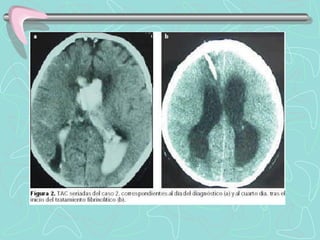

DIAGNÓSTICO

TOMOGRAFÍA COMPUTARIZADA DE ENCÉFALO

•Examen de elección en el Ictus agudo

ICTUS HEMORRÁGICO

•Lesión Hiperdensa que ocupa espacio y desplaza en

diverso grado el parénquima cerebral.

•En HSA puede ser poco hiperdensa, de ubicación

extraparenquimal, e invadir ventrículos cerebrales.

Las Neuroimágenes informan sobre el tipo de lesión, su

tamaño, localización, distribución vascular; la presencia de

complicaciones, y también sobre la necesidad de manejo

quirúrgico.